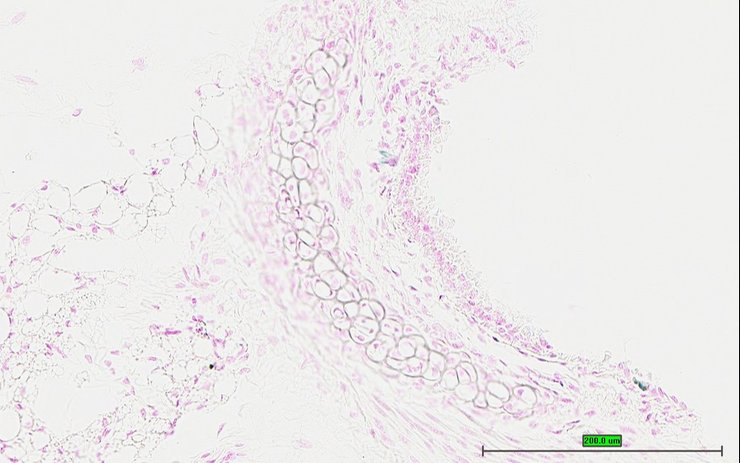

TS28: penis Present UC Davis_1883732

Specimen UC Davis_1883733: postnatal adult; Dmp1tm1.1(KOMP)Vlcg/Dmp1+ (more )

Structure Level Pattern Image Note

TS28: penis Present UC Davis_1883733

Specimen UC Davis_1883734: postnatal adult; Dmp1tm1.1(KOMP)Vlcg/Dmp1+ (more )

TS28: penis Present UC Davis_1883734

Specimen UC Davis_1883735: postnatal adult; Dmp1tm1.1(KOMP)Vlcg/Dmp1+ (more )

TS28: penis Present UC Davis_1883735